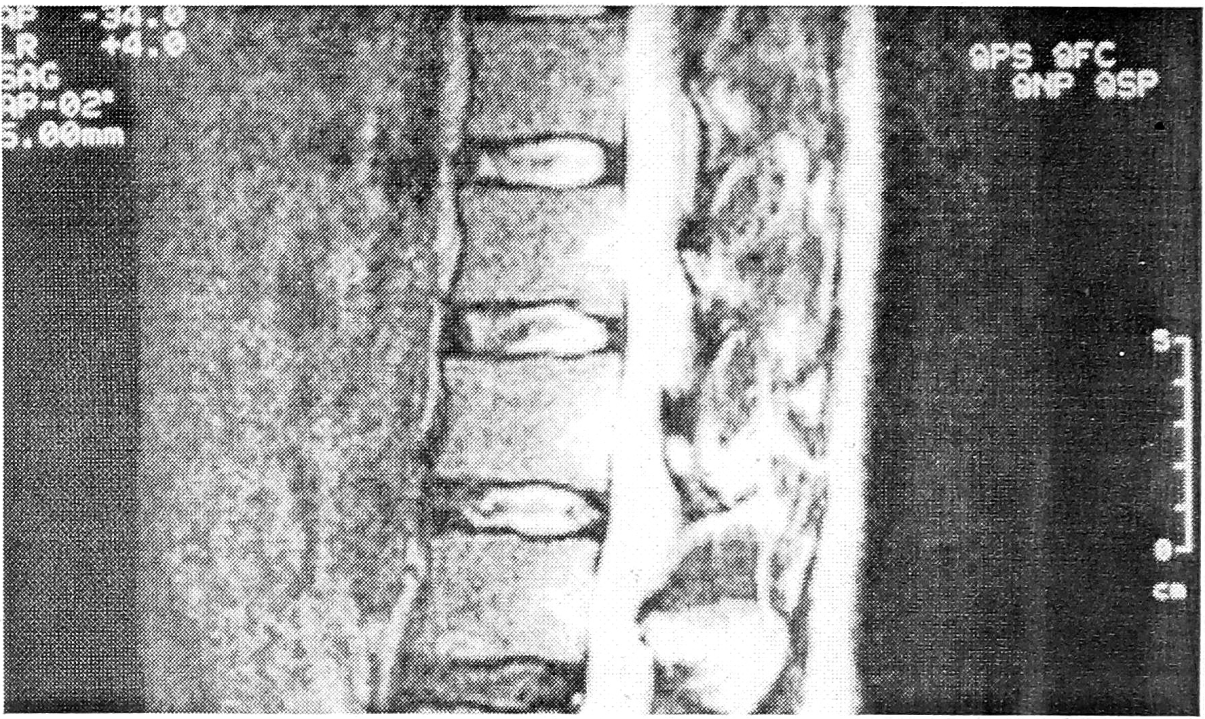

Все варианты дискограмм, относящиеся к чрездисковому типу расположения контрастного вещества, являлись специфическими для поясничной остеохондропатии и отражали диффузную дегенерацию межпозвонкового диска (см. рис. 7).

Рис. 7. Диффузная дегенерация межпозвонковых дисков при поясничной остеохондропатии.

Внеламинарный тип дискограмм наблюдался в сегментах, где имело место отделение переднего апофиза от тела позвонка, и характеризовался выпадением студенистого ядра диска между несросшимся передневерхним апофизом и передневерхним углом тела позвонка. Нуклеарная тень представляла собой протянувшуюся вдоль краниальной поверхности тела позвонка гомогенную полосу шириной 2— 3 мм. В 8 случаях отмечалось контрастирование фрагментов фиброзного кольца. Высота межтелового промежутка оказалась сниженной практически на всех дискограммах (см. рис. 8). Емкость диска составляла не менее 1,5—1,8 мл; введение контрастного вещества не сопровождалось появлением боли.

Рис. 8. Внеламинарный тип дискограмм сегментах L3—4, L4—5.